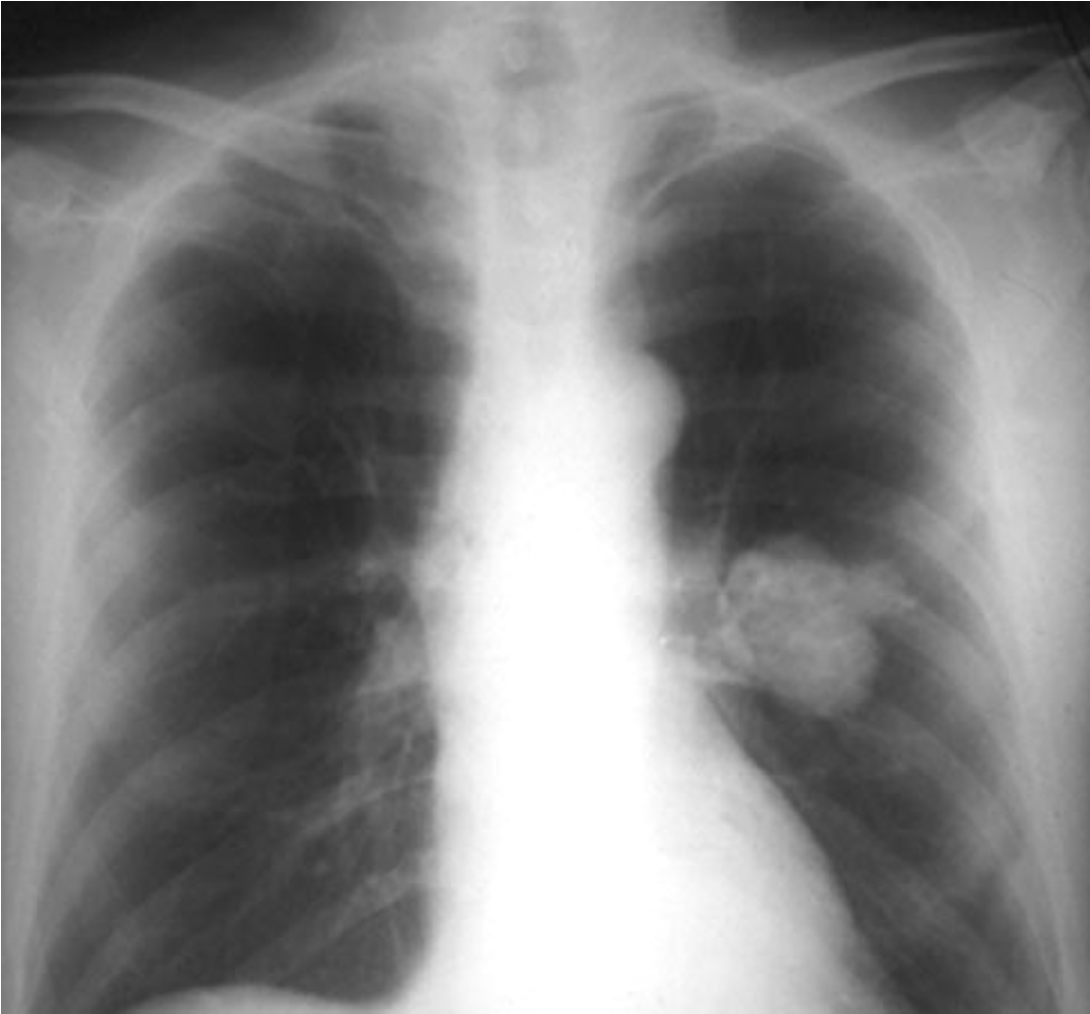

Lung Mass:

Most common type of lung cancer; usually occurring peripherally.

adenocarcinoma

Lung cancer typically occurring centrally and with cavitation

squamous cell carcinoma

What type of lung cancer is this?